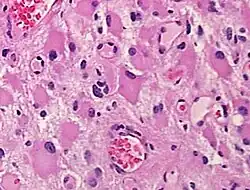

Gemistocytes are glial cells that are characterized by billowing, eosinophilic cytoplasm and a peripherally positioned, flattened nucleus. Gemistocytes most often appear during acute injury; and eventually, shrink in size.[1] They are usually present in anoxic-ischemic brains, which occurs when there is a complete lack of blood flow to the brain. Anoxic-ischemic brains usually occur in patients who have had cardiac arrest and prolonged attempt at cardiopulmonary resuscitation.[2]

When present in anoxic-ischemic brains, gemistocytes are regularly encountered in glial neoplasms, also known as glioma, which is a type of tumor that occurs in the brain and spinal cord. Usually, gliomas begin in the glial cells that surround the nerve cells to help them function. Many gliomas exhibit cells that do not exist in normal brain tissue and are not seen in glial differentiation.[1] Of these gliomas are astrocytomas, which is a type of cancer that occurs in the brain or spinal cord. The main role of astrocytes is to maintain brain homeostasis and neuronal metabolism. When the astrocytes become activated, they begin to respond to damage.[3] Astrocyte activation, known as astrogliosis, responds to neurological trauma, infections, degradations, epilepsy, and tumorigenesis. Each neurological insult plays a major role in astrocyte activation and response to that specific damage. In some astrocytomas, the number of gemistocytes is extremely overwhelming, terming it a “gemistocytic astrocytoma.” Not only are gemistocytic cells present in astrocytomas, but they are also found in various glial tumor cells; for example, oligodendrogliomas, mixed oligoastrocytomas, glioblastomas, and pleomorphic xanthoastrocytomas. Gemistocytes are known to have a large cytoplasmic mass, long, branching processes, and increased cytoplasmic filaments.[1] The cytoplasm of gemistocytes stains positive for glial fibrillary acidic protein, GFAP. While the intermediate filaments in gemistocytes are diffused throughout the cytoplasm, which indicates cellular disintegration. Within these different tumor types, the term “mini-germistocytes” is used for smaller gemistocytes, that are usually found in oligodendroglial tumors. Mini-germistocytes are found to have a very ordered arrangement of filaments throughout the cytoplasm, but may also transform into the end-state morphology of the larger gemsitocytic cells. Studies have suggested that both classic gemistocytes and mini-gemistocytes show similar genetic variation to non-gemistocytic tumor cells.[4] Mini-germistocytes, usually found in oligodendroglial tumor cells, express gliofibrillary oligodendrocytes, or GFOCs, which are capable of transforming the mini-gemistoctyes into larger gemistocytes.